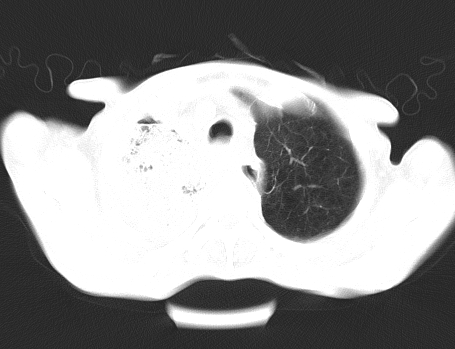

以下是引用gaoshengjiang在2008-5-30 19:53:00的发言:[br]右上叶可见大片实变影,其内可见充气支气管影及囊状影,右上叶尖端支气管走形区可见结节样影,左侧胸腔内可见胸腔胃影。纵隔淋巴结肿大。[br]考虑:1.右上肺阻塞性肺炎伴肺脓肿形成。支持转移所致。[br] 2.左侧胸腔胃。